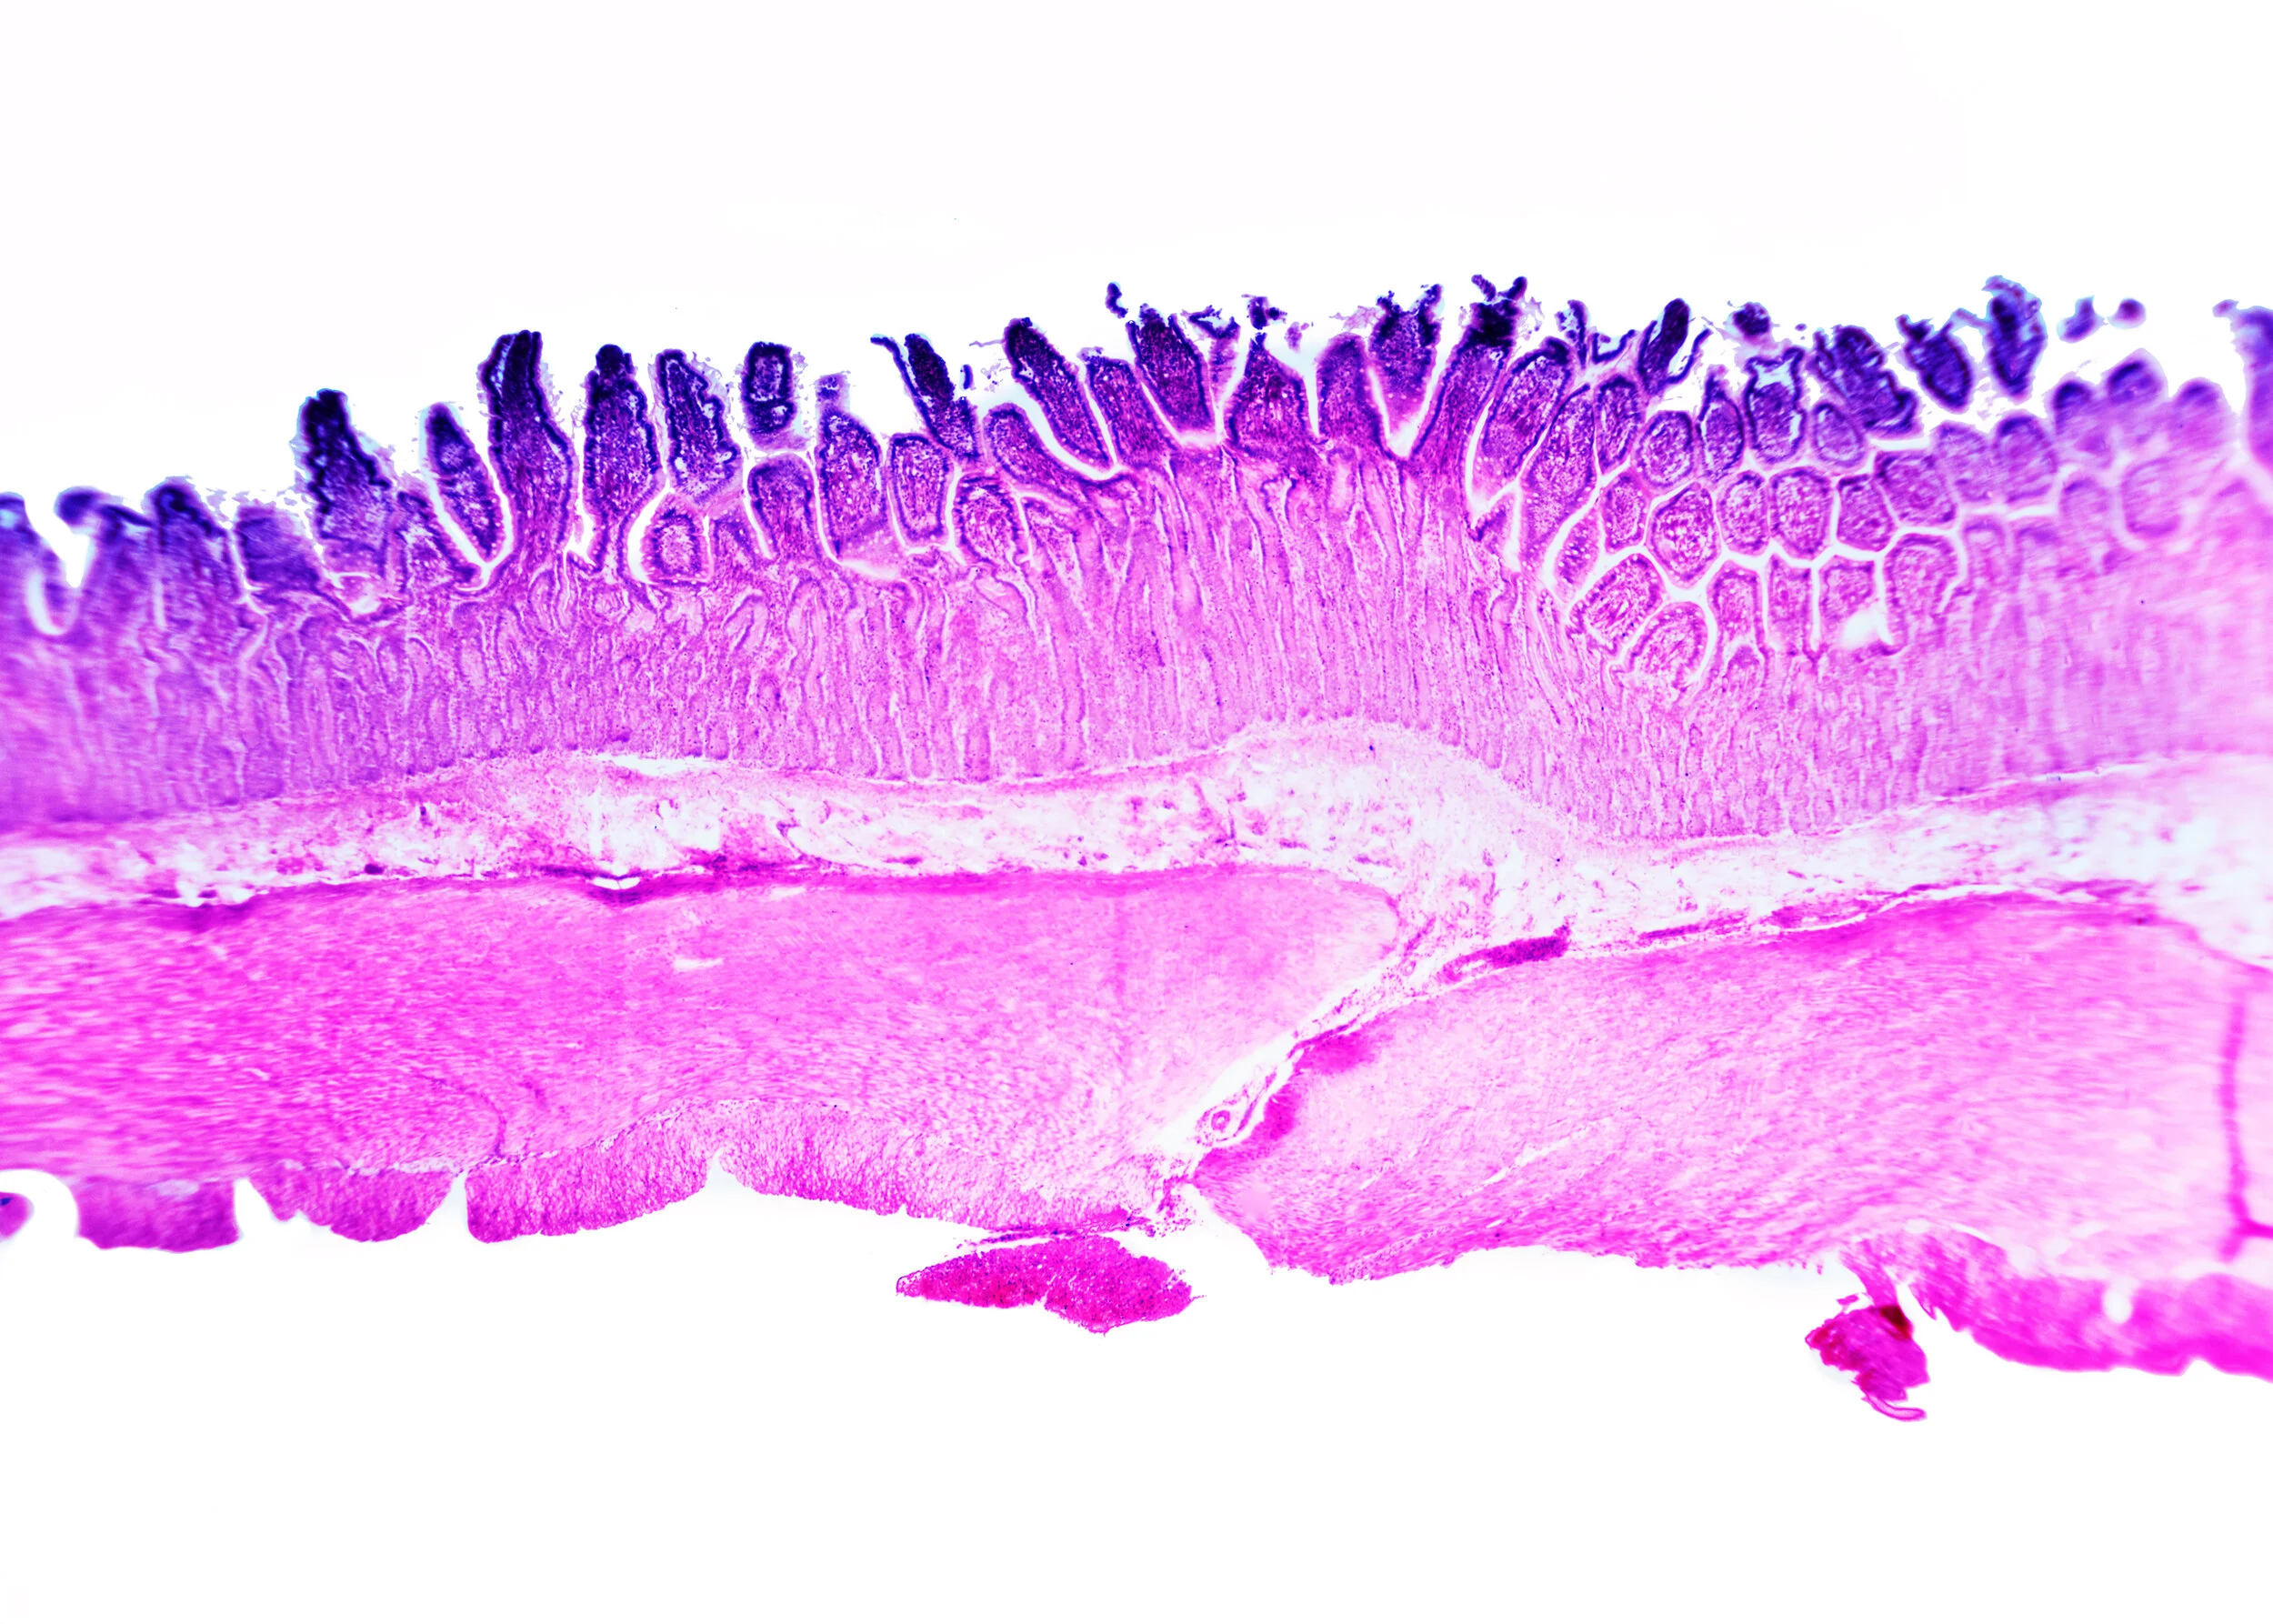

CANIS